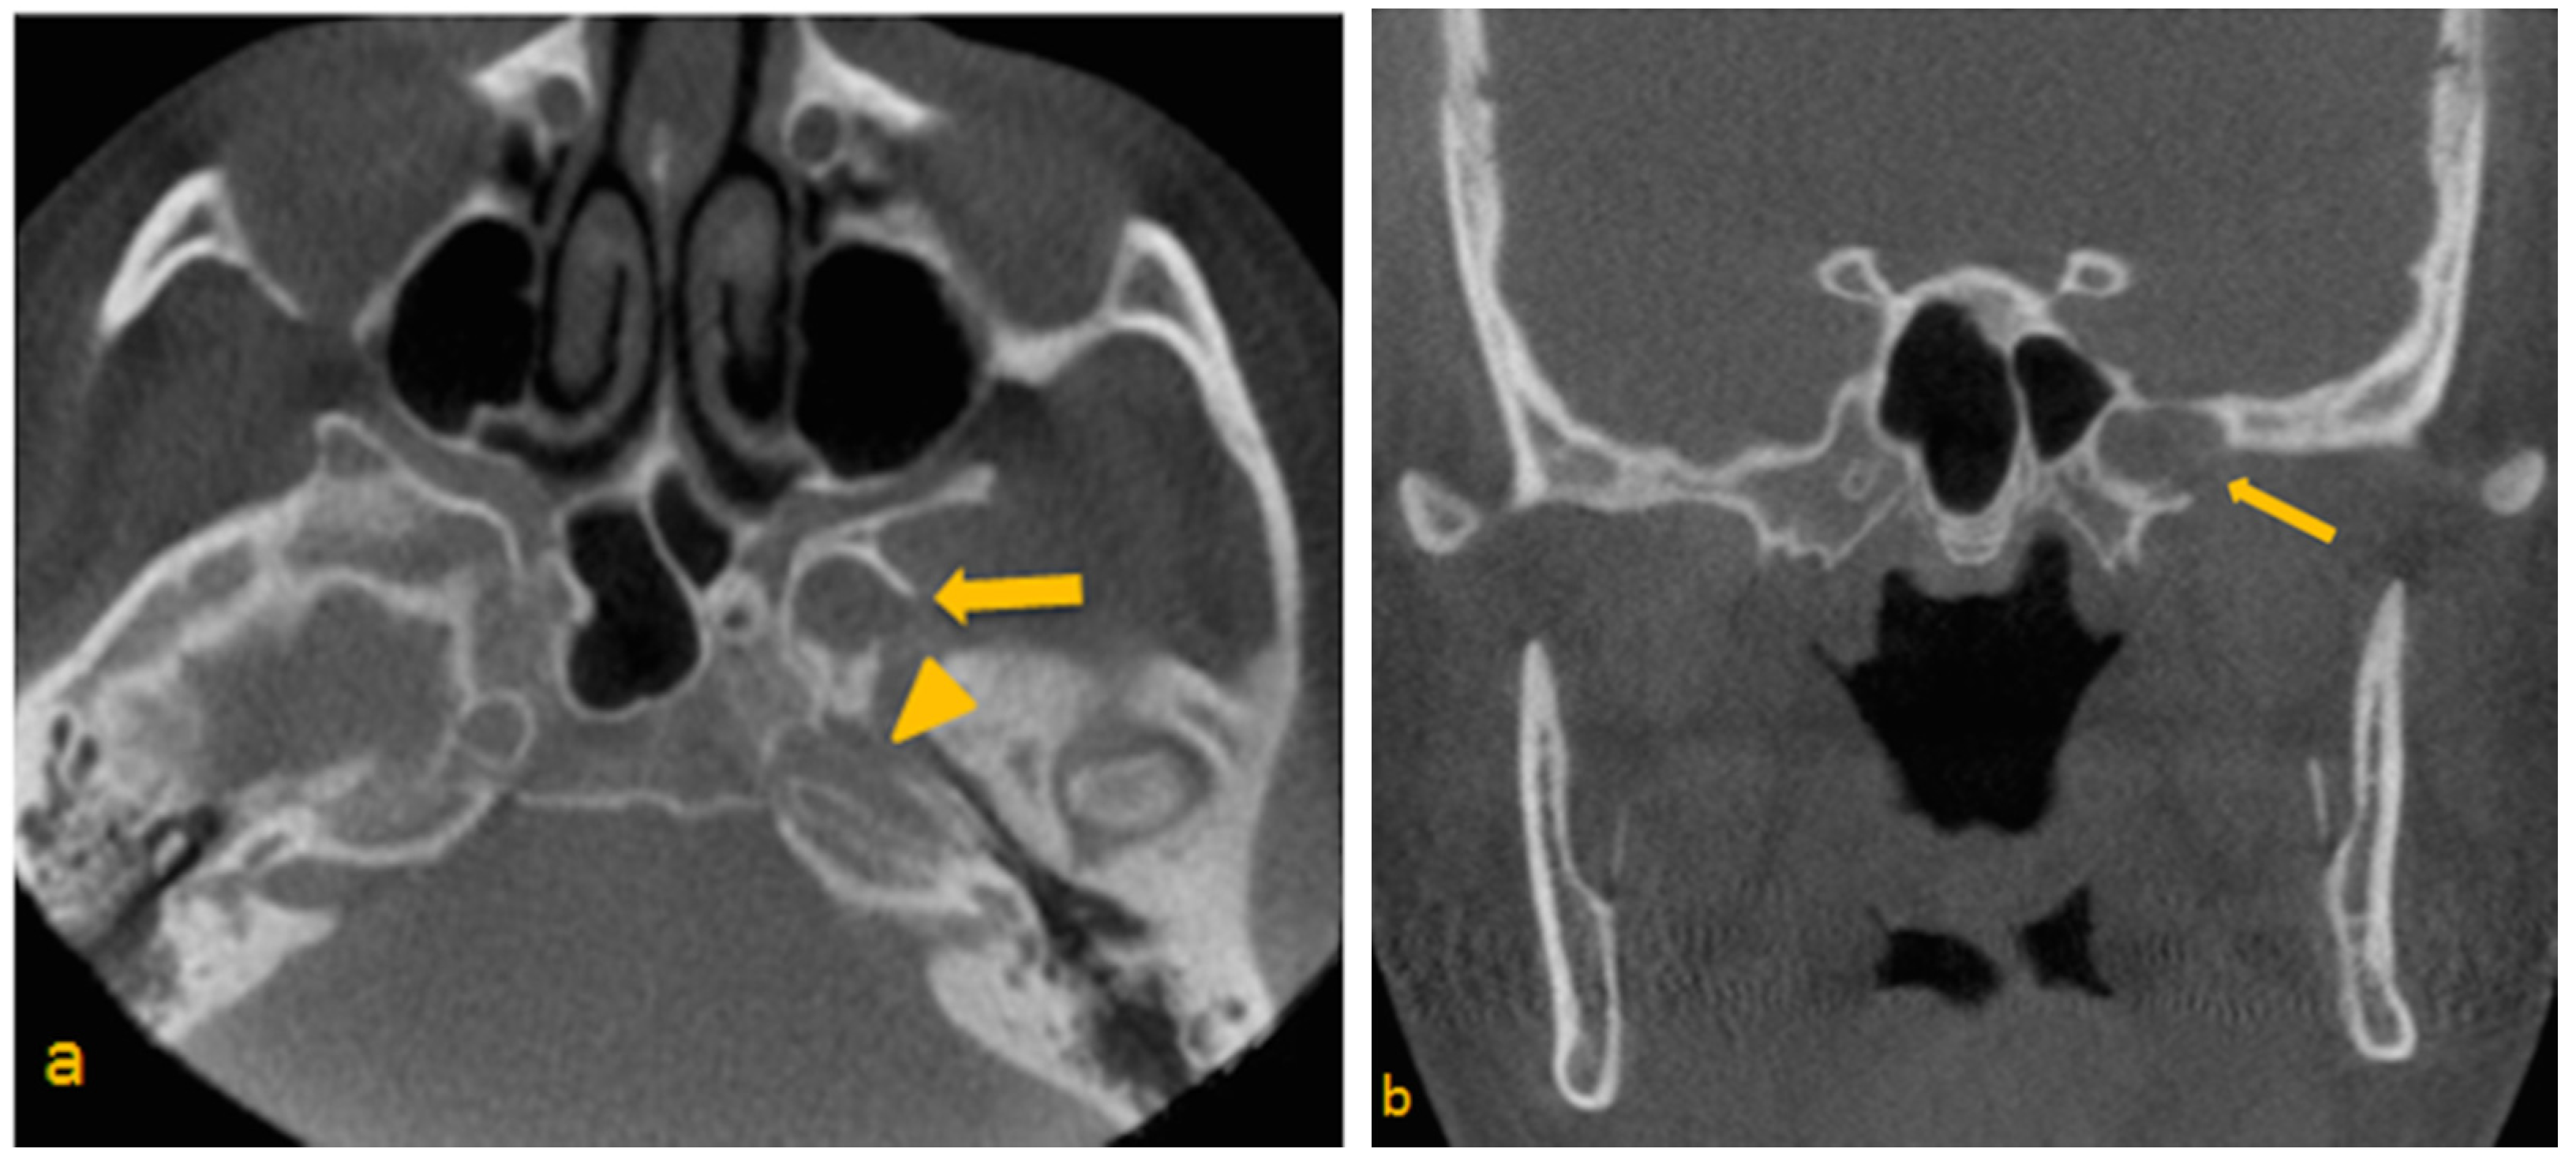

- Lesion must be non-expansile with sclerotic, well-defined margin, and should be located at a site of normal pneumatization. Evidence of fatty content should be present. Internal curvilinear calcifications should be noted on CT images [1].

- Since, sphenoid sinus is closely related to several vital neurovascular structures such as internal carotid artery and optic nerve, any associated skull-base foramina should remain intact and patent.